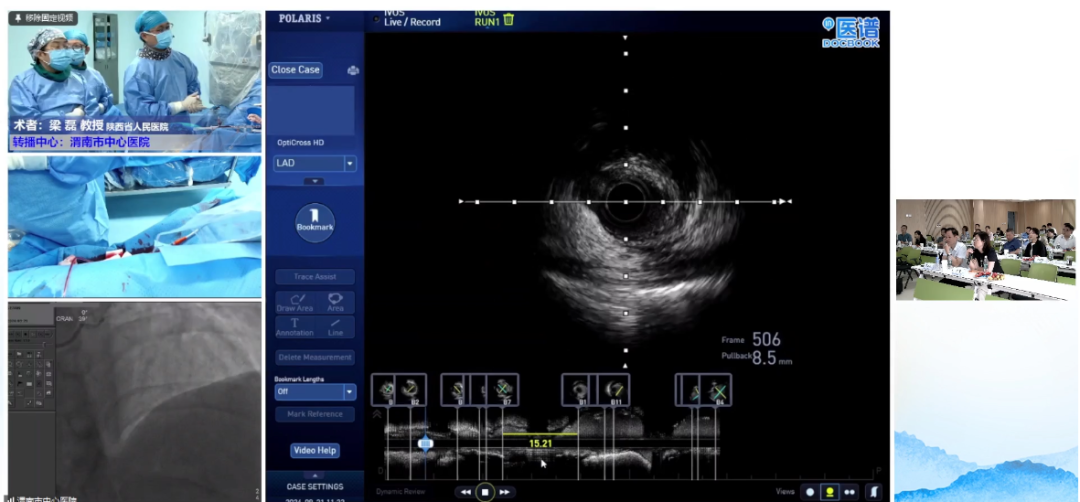

会中,郭宁教授及梁磊教授联合我院心内科介入团队对两例冠心病病人进行了介入手术治疗,并就手术进行了现场直播。

台上术者与台下专家团队就手术策略及病例难点问题进行了互动讨论,整场会议学术气氛热烈、内容丰富,为渭南市冠脉介入诊疗的规范化、精准化应用起到了提高和推动作用。